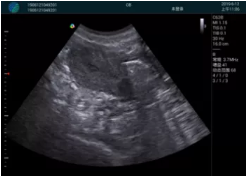

可視化甲狀腺穿刺引導(dǎo)

頸動脈血流充盈飽滿,無外溢

肝內(nèi)血管顯示清晰,血流敏感無外溢

病例二:

甲狀腺囊性結(jié)節(jié),囊壁鈣化,透聲好

甲狀腺囊性占位